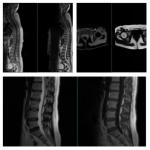

呼兰区中医医院新引进美国GE 1.5T 磁共振成像正式投入使用